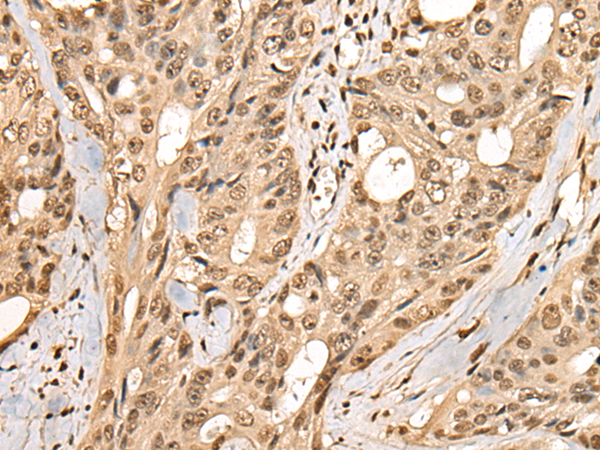

ELISA, IHC |

IHC positive control: |

Human colorectal cancer and human ovarian cancer |

IHC Recommend dilution: |

40-200 |